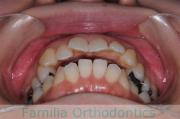

歯並びを治したいということで来院されました。下あごがやや右側に偏位して後退している、上顎前突(出っ歯)でした。上下左右から小臼歯を抜歯して、歯科矯正用アンカースクリューを併用したマルチブラケット法にて治療を行いました。約2年、24回の来院をしていただきました。

下顎の後退はいびきなどの上部気道の障害が出やすいと考えられます。